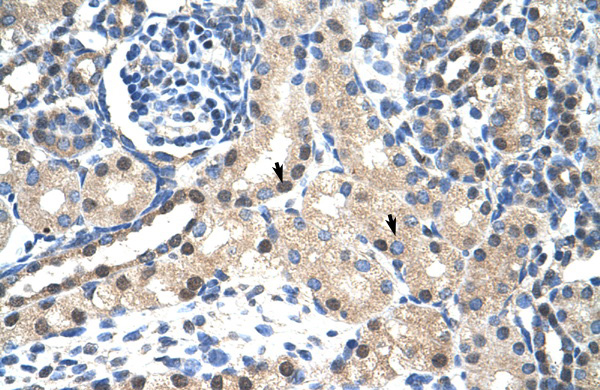

IHC (Immunohistochemistry)

(Immunohistochemistry with Pancreas tissue at an antibody concentration of 5.0ug/ml using anti-STAT1 antibody)